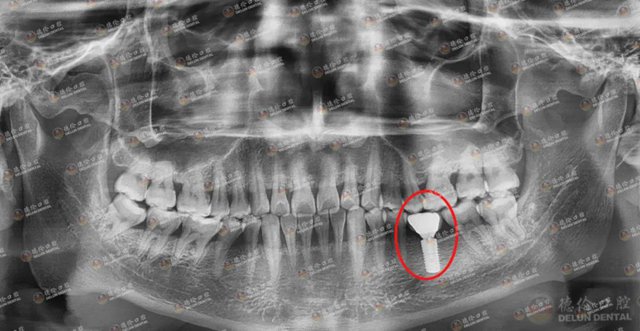

对于谢先生的恐惧与疑惑,杨主任一一讲解与安抚。终于,谢先生完成了种牙。据谢先生所说:“原来种牙一点都不害怕!无论是前期的拍片,还是植入种植体,亦或是后面的戴冠,每一个步骤杨主任都会给我详细讲解,细心安抚我。”

种牙治疗结束后,谢先生的好牙又回来了。现在的他生活过得有滋有味。这全赖于杨主任为他“种”下的一口好牙!为感谢杨主任,谢先生将锦旗赠与杨主任,向其表达浓浓的谢意。